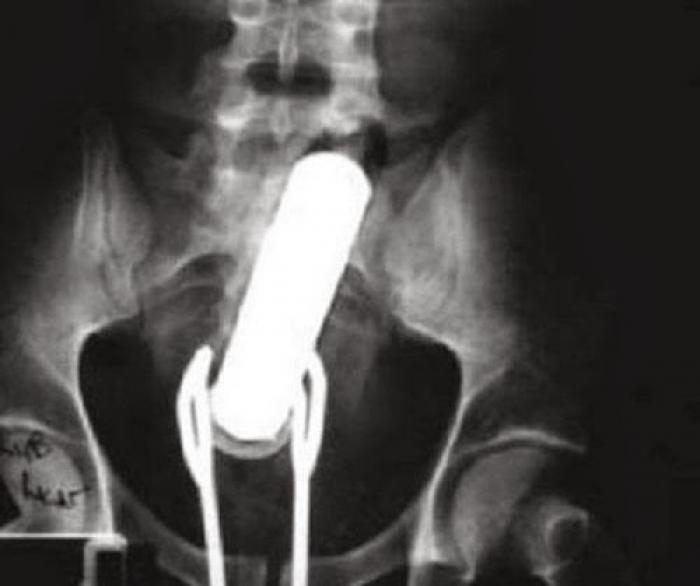

Razele X ne dovedesc că oamenii "pierd" adesea o mulțime de lucruri în propriul corp.